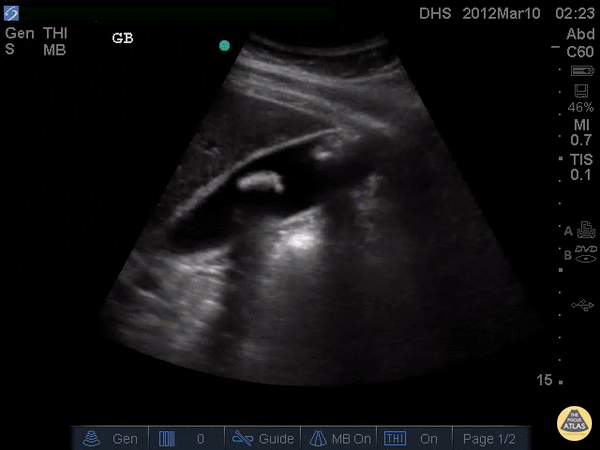

Biliary - Cholelithiasis, Not Impacted

Two large, hyperechoic stones can be appreciated in this gallbladder. These are likely two stones because of the degree of echogenicity and posterior shadowing. If you have one or two objects in the gallbladder and you're not sure if they're stones, it can be useful to have the patient lay on their side. If the objects moves when the patient moves, they are stones. If not, they are likely polyps or other masses growing from the gallbladder wall. Justin Bowra MBBS, FACEM, CCPU Emergency Physician, RNSH et al. (Dr. Darmas)